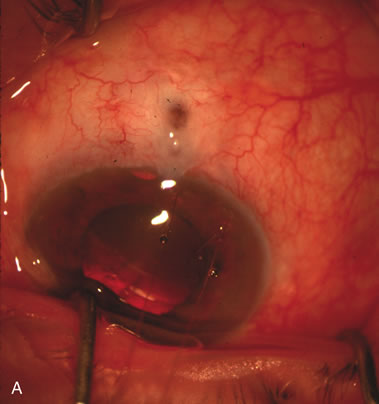

Cataract extraction by any technique performed in a patient with a pre-existing filter will have an effect on the previous filtering bleb.121–124 Bleb failure is more likely with ECCE compared with small-incision phacoemulsification.125 However, even patients undergoing topical anesthesia with clear corneal phacoemulsification and foldable IOL may experience bleb failure. One of three patients with a functioning filter and preoperative mean IOP of 12 mm Hg without antiglaucoma medications experiences bleb failure after lens extraction (Table 2). These patients require long-term drug therapy or bleb needling to control IOP. 126 Additional incisional glaucoma surgery may eventually be required in up to 10% of patients.127 Intraoperative iris manipulation may cause significant breakdown of the blood–aqueous barrier, resulting in inflammation that causes bleb failure. Even after uncomplicated clear corneal phacoemulsification, IOP may increase an average of 2 to 3 mm Hg due to bleb fibrosis.128 Approximately 20% of filtered patients require a long-term increase in glaucoma medications following uncomplicated clear corneal phacoemulsification with a foldable copolymer acrylic IOL129 (Fig. 3). In situations in which the bleb is not working at all, the eye will have a postoperative pressure spike that mimics that in the patient not having had a prior filtering procedure. In situations in which the bleb is marginal, the pressure spikes tend to be lower, and the final postoperative IOP tends to be around 50% higher than it was preoperatively. These patients require combined procedures in order to reestablish long-term filtration. In situations in which the bleb is very thin, polycystic, and associated with an IOP around 5 to 8 mm Hg on no antiglaucoma therapy; uncomplicated cataract extraction will have a minimal effect on the level of IOP. Patients with functioning glaucoma drainage implants usually have minimal long-term changes in IOP after uncomplicated cataract extraction.130

Fig. 3. Partial bleb failure following clear corneal phacoemulsification with foldable IOL. A. Preoperative bleb appearance prior to temporal lens extraction. Preoperative IOP was 12 mm Hg on no antiglaucoma medications. Time from 5-FU trabeculectomy surgery to lens extraction was one year. B. Bleb appearance 2 months after clear corneal cataract surgery with topical anesthesia. Following lens extraction, increased vascularity was noted along with decreased size of the filtering bleb. IOP increased to 20 mm Hg as early as 2 weeks after surgery, necessitating topical antiglaucoma therapy. C. High magnification view of bleb before lens extraction demonstrates diffuse pale bleb. D. High magnification view of bleb 2 months after surgery. There are vessels surrounding the nasal side of the bleb and the overall bleb size is smaller.